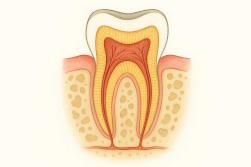

La dévitalisation, ou traitement endodontique, consiste à retirer le nerf d’une dent puis à obturer les canaux. Cette intervention permet d’éliminer la douleur et de sauver la dent. Après ce soin dentaire, il est normal de ressentir une sensibilité ou de légères douleurs résiduelles.